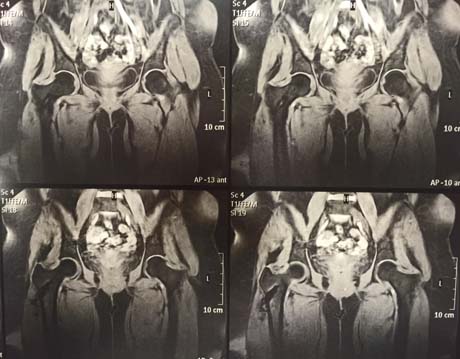

MRI: left femoral head osteonecrosis (white arrow)

Magnetic resonance imaging of the hip after 5 months post-op and the injection of stem cells. Osteonecrosis of the femoral head has subsided completely. The patient is fully cured.